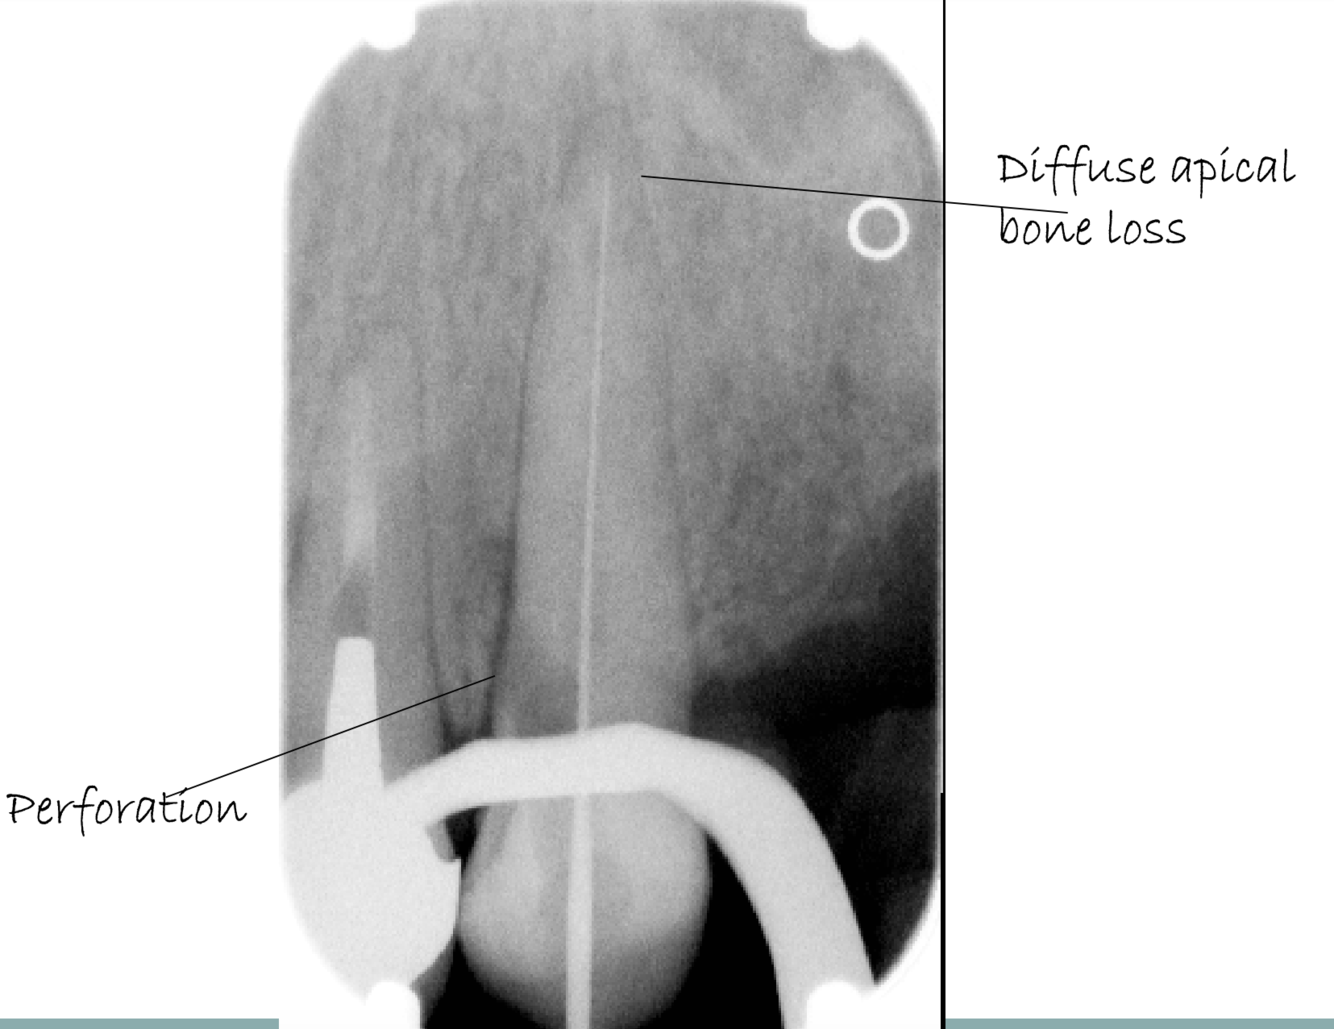

What can you see at the Initial spread of inflammation?

Loss of lamina dura at apex

What can you see in Further inflammatory spread?

Periapical bone loss

What can you see in Initial chronic inflammation?

What can be seen in Chronic inflammation - long standing?

Circumscribed, well defined, radiolucent area periapically with sclerotic bone surrounding

radiolucency sometimes described as rarefying osteitis